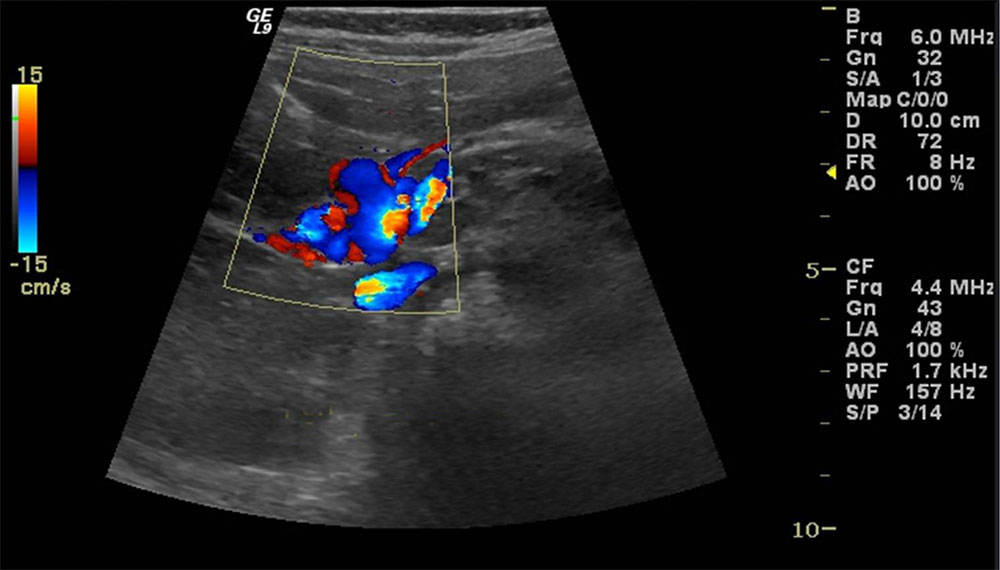

Renkli Doppler Ultrasonografi

Ultrasonografi yüksek frekanslı ses dalgaları kullanılarak vücut içinde organların görüntülenmesidir. Önce prob aracılığı ile ses dalgaları gönderilir. Aynı şekilde geri dönen ses dalgaları, prob tarafından toplanıp elektrik enerjisine dönüştürülür. Bilgisayar aracılığı ile de görüntü haline getirilir. Vücudun birçok bölgesinin incelenmesinde kullanılır. Başlıca kullanım alanları; karın içi organlar, tiroid bezi, meme gibi yüzeyselorganlar, gebelik takibi, kalp, atar-toplar damarlar olarak özetlenebilir.